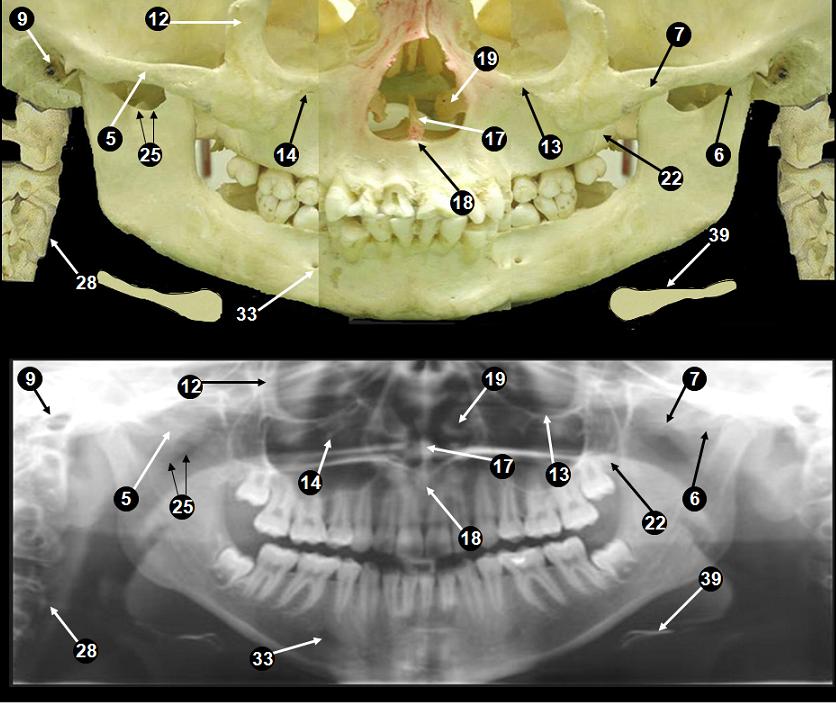

Anatomical landmarks evaluated on the panoramic radiogr .... It is our preferred view for the initial exam as it gives us a quick and easy. The medical mentors on instagram: Your dentist will recommend appropriate radiology according to any conditions they need to assess. Automatic segmentation of mandible in. Collection by dekwatt ramaar • last updated 4 weeks ago. It depicts the teeth & the supporting bones of the upper and lower jaw, in addition to the the jaw joints on either side. Due to variations of human anatomy and different head poses. Advantages of panoramic radiography• field size• quality control• simplicity• time & rapidity of the procedure• client cooperation• dose• minimal infection control• gross anatomy & pathology visible ikassem@dr.com. Of patients during radiography, they need to be taken into. This important diagnostic tool is. This provides a quick photo of the teeth to help the dentist determine potential tooth decay. Want to review the anatomy of the carpal bones? Features of the dentition to be compared in the assessment. 39 companies | 109 products. This great post by @theradiologistpage helps tremendously!

Normal Anatomic landmarks on Panoramic Radiograph - Dental .... Features of the dentition to be compared in the assessment. The medical mentors on instagram: Of patients during radiography, they need to be taken into. Due to variations of human anatomy and different head poses. Your dentist will recommend appropriate radiology according to any conditions they need to assess. Collection by dekwatt ramaar • last updated 4 weeks ago. 39 companies | 109 products. Automatic segmentation of mandible in. Want to review the anatomy of the carpal bones? This important diagnostic tool is. This great post by @theradiologistpage helps tremendously! Advantages of panoramic radiography• field size• quality control• simplicity• time & rapidity of the procedure• client cooperation• dose• minimal infection control• gross anatomy & pathology visible ikassem@dr.com. It is our preferred view for the initial exam as it gives us a quick and easy. It depicts the teeth & the supporting bones of the upper and lower jaw, in addition to the the jaw joints on either side. This provides a quick photo of the teeth to help the dentist determine potential tooth decay.